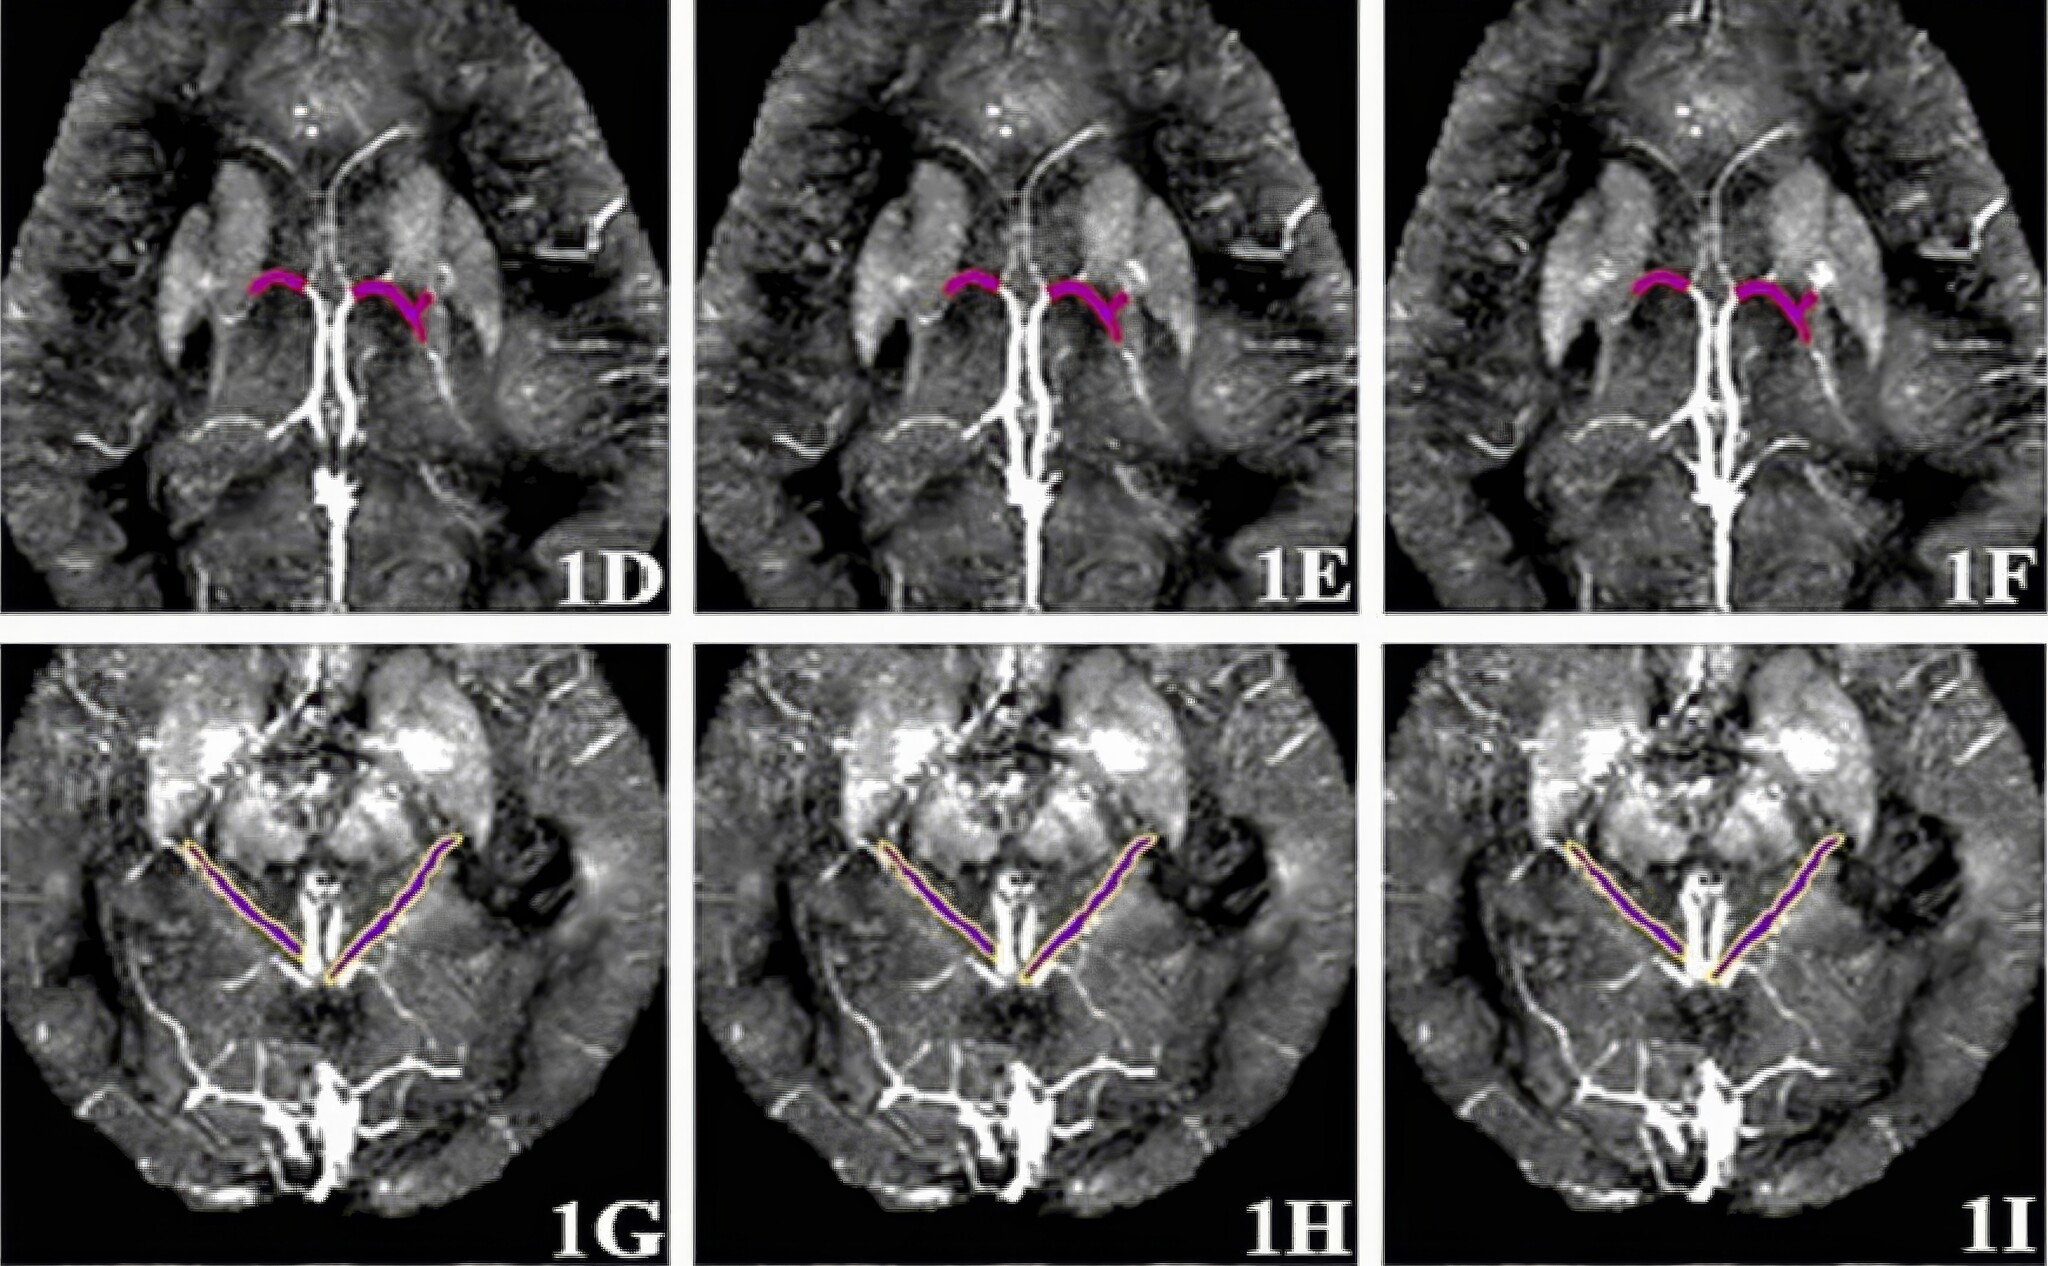

Разработка ученых Пермского Политеха позволяет диагностировать болезнь Альцгеймера, когда её ещё можно замедлить или предотвратить. Способ основан на данных магнитной восприимчивости (МВ) вен головного мозга – физической величине, которая характеризует толщину вен. Магнитные свойства зависят от белка (гемоглобина). Сам по себе он обладает низкой МВ, и малое значение показателя означает, что кровь хорошо циркулирует по венам. В обратном случае – значение будет высоким: из-за утолщенных стенок вена становится узкой, и по ней проходит мало белка.

– Мы проанализировали данные 81 пациента, давших согласие на публикацию их медицинских сведений, и выяснили, что есть две вены, которые являются наиболее информативными. А именно: базальные вены и вены таламуса в левом и правом полушариях головного мозга. Ранее это было неизвестно. В этом заключается первое принципиальное отличие нашего метода от существующих, – поделился начальник управления организации научных исследований ПНИПУ Александр Алексеев.